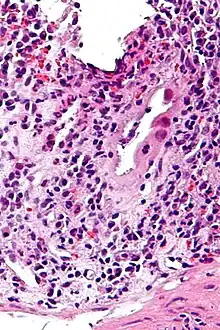

Micrograph of CMV colitis. H&E stain.

CMV colitis may be clinically manifested with diarrhea (usually non-bloody), abdominal pain, weight loss and anorexia. The diagnosis of CMV colitis is based on serology, CMV antigen testing and colonoscopy with biopsy. Clinical suspicion should be aroused in the setting of immunocompromised patient but it is much rarer in immunocompetent patient. Although it is known that CMV colitis is almost always caused by reactivation of latent CMV infection in immunocompromised patients, new infection of CMV or reinfection of different strain of CMV can cause colitis in immunocompetent hosts. Because asymptomatic CMV viremia and viruria is common and about 1/3 of symptomatic CMV infection is caused by reinfection of different strain of CMV, the diagnosis of CMV colitis needs more direct causality. It is practically achieved by colonoscopy or sigmoidoscopy tissue sampling and pathological evidence of CMV infection under microscope, more specifically macroscopic picture will show many ulcers that appear on the mucous membrane and microscopically the biopsy will show intranuclear and cytoplasmic inclusion bodies. Positive CMV IgG doesn't necessarily mean that it is reactivation of latent infection because of the possibility of reinfection of different strain.